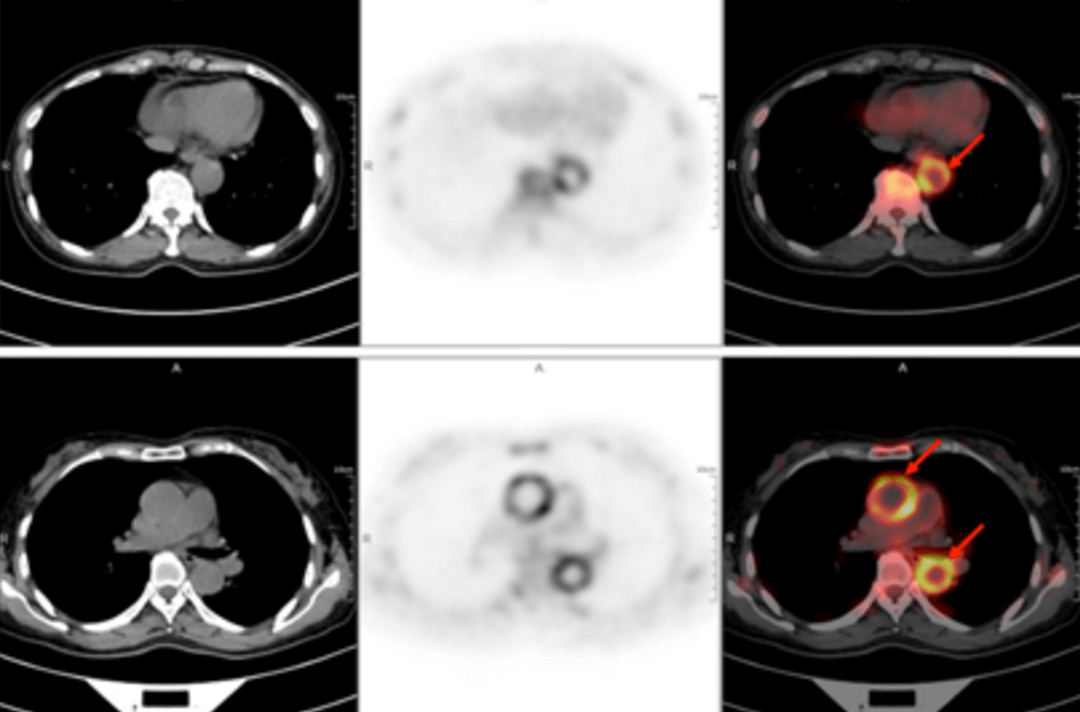

A 58-year-old women went to the hospital for intermittent fever for more than 40 days. Her highest body temperature was 38.9℃. Other symptoms included fatigue and shoulder joint pain which were especially acute in the afternoon and at night without cold, chills, sputum, hemoptysis, chest pain, chest tightness and shortness of breath. After two weeks of intravenous administration of "cephalosporin antibiotics" there was no improvement, and intermittent fever continued. The outpatient clinics noted the patient had "fever of unknown origin." There were no obvious diagnostic features upon physical examination. The results of a routine blood test were as follows: erythrocyte sedimentation rate in the first hour: 72mm; high-sensitivity C-reactive protein: 204. 20mg/l. Then, the patient had a whole-body F-FDG PET-CT examination to find the cause of the fever of unknown origin.

In the PET/CT images, wall thickening with increased glucose metabolism occurred in several parts of the body (bilateral internal carotid artery, common carotid artery, brachiocephalic trunk, bilateral subclavian and axillary arteries, thoracic aorta, abdominal aorta, bilateral common iliac artery, internal iliac artery, external iliac artery and femoral artery), which was considered to be caused by inflammatory changes. Combined with the patient's medical history, clinical symptoms, examination and imaging findings, she was diagnosed with T.A. After standardized anti-inflammation treatment, her body temperature dropped and her condition improved.